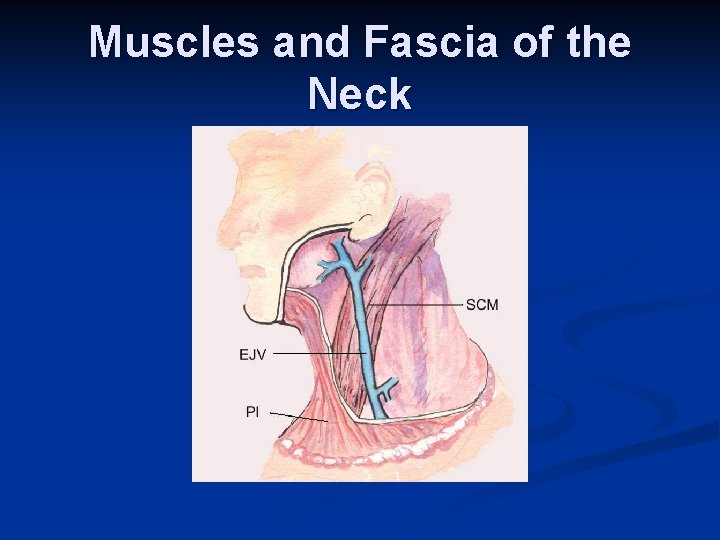

Muscles and Fascia of the Neck

Deep dissection of neck. BIF = bifurcation, SCM= sternocleidomastoid, TM= trapezius muscle